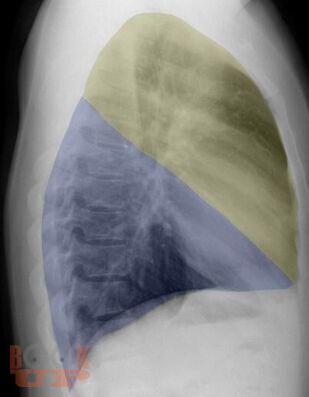

В учебном пособии представлена информация о нормальной рентгеновской анатомии органов грудной полости, вариантной анатомии, наиболее частых аномалиях развития, скиалогии, алгоритме описания рентгенограмм и основных требованиях по оформлению протокола рентгенологического исследования.